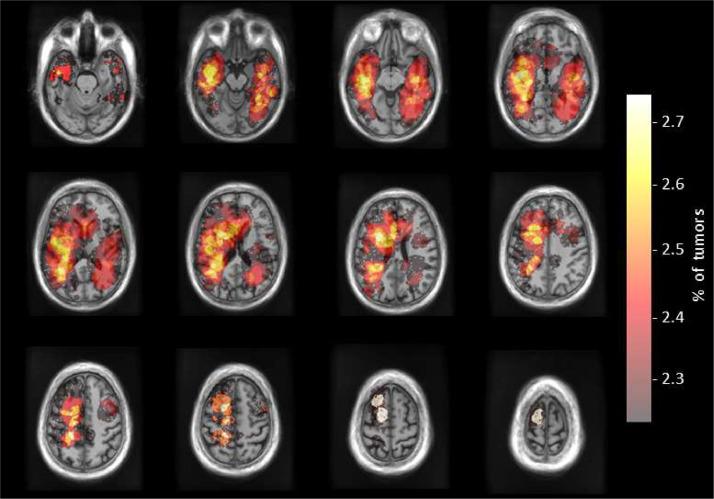

Glioblastoma, a highly aggressive primary brain tumor, is associated with poor patient outcomes. Although magnetic resonance imaging (MRI) plays a critical role in diagnosing, characterizing, and forecasting glioblastoma progression, public MRI repositories present significant drawbacks, including insufficient postoperative and follow-up studies as well as expert tumor segmentations. To address these issues, we present the "Río Hortega University Hospital Glioblastoma Dataset (RHUH-GBM)," a collection of multiparametric MRI images, volumetric assessments, molecular data, and survival details for glioblastoma patients who underwent total or near-total enhancing tumor resection. The dataset features expert-corrected segmentations of tumor subregions, offering valuable ground truth data for developing algorithms for postoperative and follow-up MRI scans.